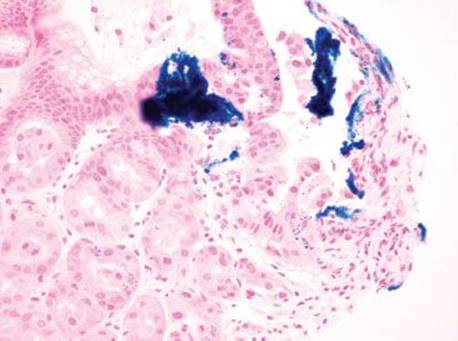

Figure 2.232 Iron pattern B/“iron pill gastritis” (Prussian blue). A Prussian blue highlights the iron. As characteristic for pattern B, the iron is predominantly extracellular, embedded in the superficial mucosa, and within the luminal space.

Gastric iron deposition is seen in up to 3.8% of upper tract biopsies (Fig. 2.228).23,24,183–185 In a study of 500 gastric biopsies, the deposition was demonstrated in three generalized patterns. Pattern A (also referred to as “nonspecific gastric siderosis”) was the most common subpattern and involved 2.2% of specimens (Figs. 2.229 and 2.230). This subpattern was associated with prior mucosal microhemorrhages, and the subtle depositions were predominantly identified within macrophages and stromal cells of the lamina propria. Pattern B (also referred to as “iron pill gastritis”) was seen in 0.8% of the biopsies and was consistently associated with ferrous sulfate therapy. This deposition was coarse and crystalline and predominantly identified in the extracellular and most superficial aspect of the biopsy (Figs. 2.231–2.234). In this subpattern, the background mucosa had a reactive gastritis/gastropathy pattern with erosions, ulcerations, and fibrino-inflammatory exudate common. In a separate study of 1,300 gastric biopsies, a similar “iron pill gastritis” injury pattern was detailed.184 This latter group reproduced the identical iron deposits in the laboratory by oxidizing ferrous sulfate tablets, providing clear evidence for the iron origin of these deposits. The mechanism of injury is a bit unclear in this subpattern. Some speculate that the iron pill has a direct caustic effect on the adjacent mucosa, whereas others suggest that the iron deposits may simply colonize previously injured mucosa. Pattern C (also referred to as “gastric glandular siderosis”) was the least common pattern, involving 0.6% of the specimens. This subpattern was associated with iron overload settings, such as hereditary hemochromatosis and multiple blood transfusions. The characteristic deposits were subtle, uniform, and identified in the deep antral and oxyntic glands (Figs. 2.235–2.239). The iron deposits can be highlighted blue with a Prussian blue iron special stain. Recognition is important to help prevent further injury and potential stricture formation (pattern B), to suggest pertinent iron overload evaluation (pattern C), and to avoid overdiagnosing the marked reactive epithelial change as dysplasia.

• Pattern B/“iron pill gastritis” features coarse, crystalline deposits in the extracellular space and most superficial aspects of the biopsy.